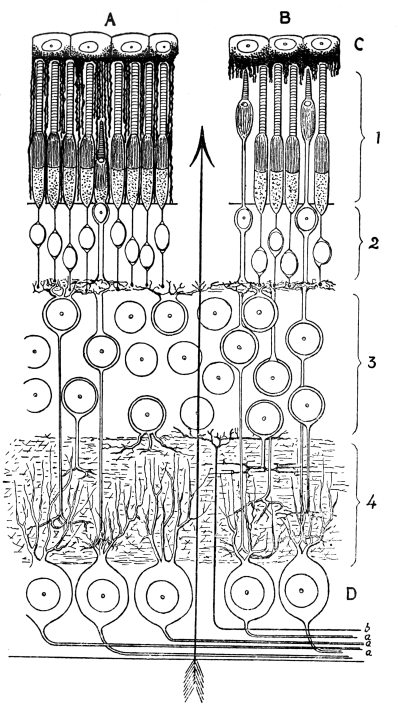

| 30. | Retina adapted for Obscurity and for Bright Light | 377 |